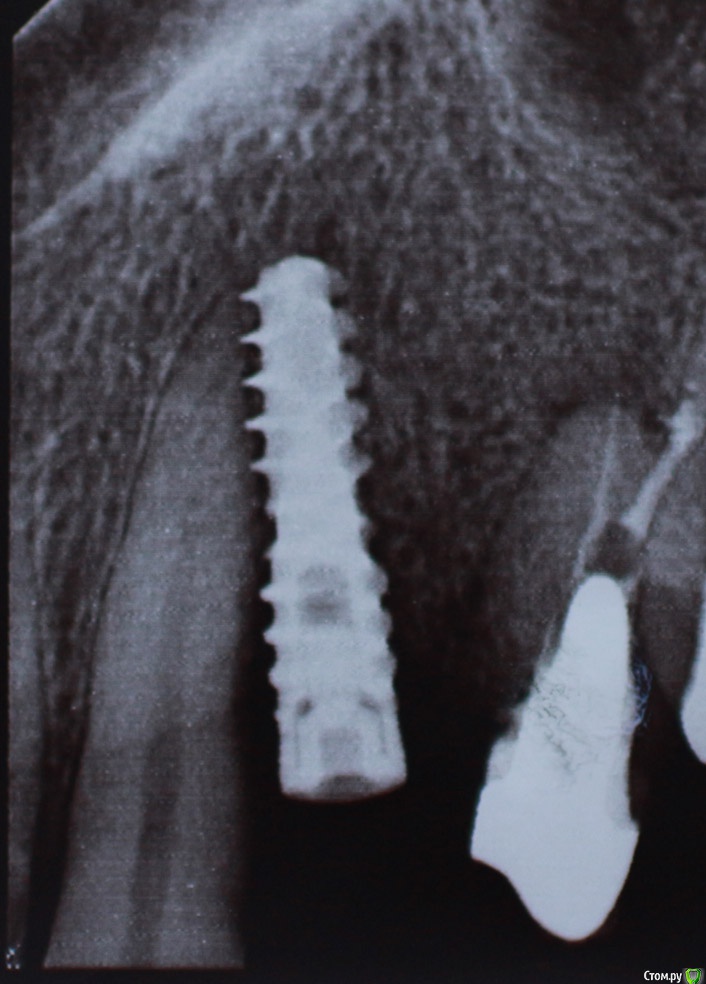

alex_ddd Опубликовано 26 июля, 2016 Поделиться Опубликовано 26 июля, 2016 имплант поставили 3 недели назад... сегодня сделал снимок. ((( выкручивать? и что будет с 3-ой? все это время при надавливании на нее неприятные ощущения. Ссылка на комментарий

gum Опубликовано 26 июля, 2016 Поделиться Опубликовано 26 июля, 2016 Если клык беспокоит, то лучше переустановить имплантат. Имейте ввиду, что данный снимок не даёт четкого расположения имплантата относительно зубов. Ссылка на комментарий

alex_ddd Опубликовано 26 июля, 2016 Автор Поделиться Опубликовано 26 июля, 2016 да, остается надежда не перекрытие планов Ссылка на комментарий

alex_ddd Опубликовано 26 июля, 2016 Автор Поделиться Опубликовано 26 июля, 2016 (изменено) но я не могу сказать, что клык беспокоит, ноет или еще как.. после операции было ощущение что на зуб надавили и он отходит. сейчас небольшая боль при надавливании.а КТ покажет, поврежден ли зуб? или только время..? Изменено 26 июля, 2016 пользователем alex_ddd Ссылка на комментарий